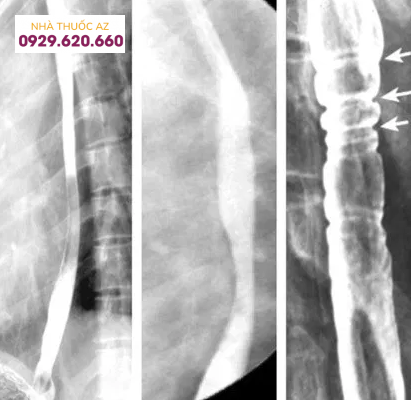

Hình 5. Hình ảnh các vòng thực quản trên chụp Baryt, tương ứng với các vòng tròn đồng tâm của thực quản được nhìn thấy trên nội soi

Hình 6: Hình ảnh các vòng thực quản trên chụp Baryt ở một bệnh nhân bị viêm thực quản bạch cầu ái toan (Nguồn: abdominalkey.com)

Hình 7. Hình ảnh các vòng thực quản trên chụp Baryt, vòng thực quản cũng là hình ảnh hay gặp với nhiều thuật ngữ được sử dụng như “khí quản hóa thực quản” hay “thực quản dạng vòng”. (Nguồn: en.wikipedia.org)

Đường kính của đoạn hẹp trung bình khoảng 1cm và vị trí hẹp ở phía đoạn thực quản trên/giữa có xu hướng dài hơn so với đoạn dưới. Tùy vị trí đoạn hẹp trên chụp Baryt vẫn cần cân nhắc đến các chẩn đoán phân biệt khác. Các nguyên nhân khác gây hẹp ở đoạn thực quản trên hoặc giữa bao gồm thực quản Barrett, xạ trị vùng trung thất, sử dụng một số loại thuốc như NSAID, quinidine, trong khi hẹp ở đoạn dưới thực quản có thể do viêmthực quản trào ngược. Cần chú ý những bệnh nhân có hình ảnh hẹp thực quản trên chụp Baryt thường có triệu chứng nuốt khó và đây chỉ là một dấu hiệu gợi ý, cần kết hợp nhiều yếu tố liên quan đến bệnh sử, triệu chứng lâm sàng, hình ảnh nội soi và mô bệnh học.Vòng thực quản cũng là hình ảnh hay gặp với nhiều thuật ngữ được sử dụng như “khí quản hóa thực quản” hay “thực quản dạng vòng”. Vị trí và sự phân bố của các vòng thực quản rất khác nhau trên nội soi, có thể ở các đoạn của thực quản hoặc phân bổ lan tỏa nhiều chỗ. Đôi khi những vòng này có thể gây hẹp khiến dây sợi khó đưa qua được. Trên chụp Baryt, các vòng này thường nhiều, hay xuất hiện gần nhau, có dạng đồng tâm dọc theo lòng thực quản.